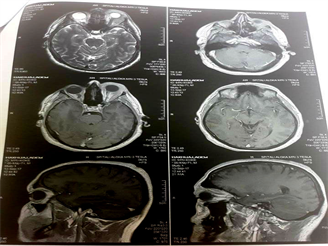

RTG pulmo had no significant changes. Cranio-orbital MRI revealed no intracranial involvement with suspicion of preseptal/orbital cellulitis and differential diagnosis for pseudotumor or lymphoma (Figure 3).

Figure 3. Initial Cranio-orbital MRI.

Figure 6. Second Cranio-orbital MRI.

In meanwhile, the proptosis advanced with dislocation down and nasal, with no motility movement, no pupillary reaction, cornea exposal and amaurotic eye (Figure 5). Second cranio-orbital MRI revealed still no intracranial involvement, but morbid progression of the diseases (Figure 6).